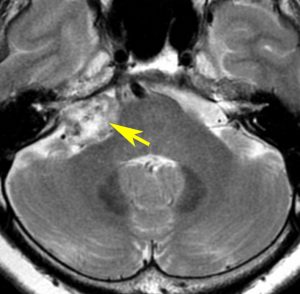

また,この患者さんは急に容態が悪くなって意識障害となりました。何故なら腫瘍の内部で出血したからです(黄色の矢印の部分)。第4脳室が詰まって閉塞性水頭症になって側脳室が拡大しています(右の画像)。

大きなのう胞性聴神経腫瘍です。いくつかの袋が重なって腫瘍を形成しています。橋や延髄(脳幹部)が変形して,第4脳室がつぶれて閉塞しています。袋の周りが白く線状に造影されているのですが,この袋の壁だけに腫瘍細胞がありますから,これを剥がすように摘出します。顔面神経が薄くなって袋の壁にくっついているのですが,袋を破ってくしゃくしゃにすると顔面神経の位置が変わってしまって,顔面神経を損傷することがあるので要注意です。のう胞性聴神経腫瘍の方が顔面神経麻痺の後遺症の頻度が高いという報告もあるくらいです。この患者さんは迷走神経と舌咽神経の圧迫も強くて,ご飯を飲み込むことが難しくなっていました(嚥下障害)。